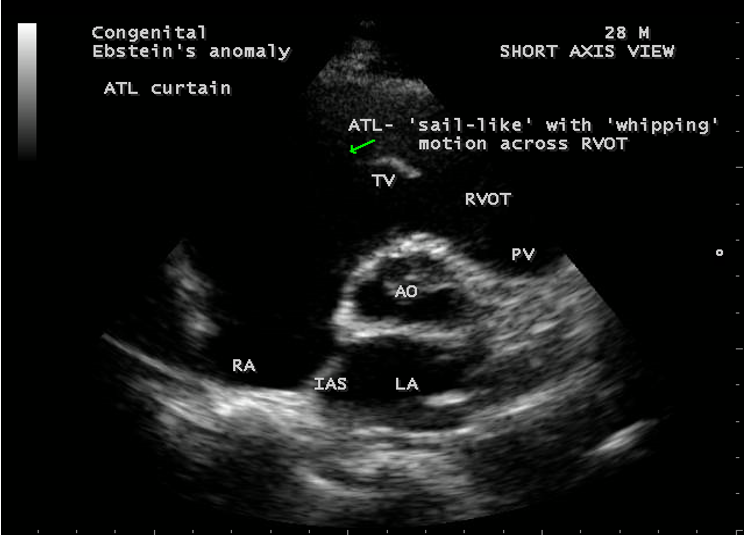

A 28-year old male presented with cyanosis and auscultation revealed a ‘sail sound’ ( loud tricuspid component of first heart sound due to increased tension developed by the large anterior leaflet as it reaches the limits of its systolic excursion- an important sign of anterior leaflet mobility), a ‘cadence’ quality of quadruple rhythm due to wide splitting of first and second sounds ( due to complete right bundle branch block), atrial and ventricular filling sounds (summation of these sounds due to prolonged PR interval). ECG revealed the features of Ebstein’s anomaly as shown in Figures 11 and 12. X-ray chest revealed the Ebstein’s configuration as shown in Figure 13. 2D echocardiography revealed a ‘sail-like’anterior tricuspid leaflet forming a ‘muscular curtain’ in between the inflow and trabecular parts of the right ventricle as an ‘imperforate membrane’ with a ‘pinhole’communication, associated with a muscular VSD (ventricular septal defect) in the proximal, atrialized compartment of right ventricle suggesting an ‘atretic” (‘imperforate’) Ebstein’s anomaly as shown in Figures 14 to 27.

The anterior tricuspid leaflet is not involved in the process of downward displacement, it may be abnormally inserted occasionally and Shiina, et al documented the apical displacement of anterior tricuspid leaflet in 14% of cases echocardiographically [39]. The anterior leaflet forms a large, sail-like intracavitary curtain as in Figures 14, 25 and contains muscular strands instead of consisting entirely of a fibrous membrane as in the normal tricuspid valve [40]. It is potentially mobile with a brisk sail-like movement as shown in Figure 21 to 24 [41], free bloating with a ‘whipping motion’ across the right ventricular outflow tract (RVOT) as shown in Figure 26 and in some cases, the movement is restricted due to its adherence to the ventricular wall as in Figure 1 and 2, 4 and 9. It is often fenestrated, may in part be musculaized , inserting into the trabeculations of the right ventricle (RV) as in Figure 28 and rarely, the anterior leaflet forms an ‘atretic’ membrane that spans the midportion of the right ventricular cavity as in Figure 16.